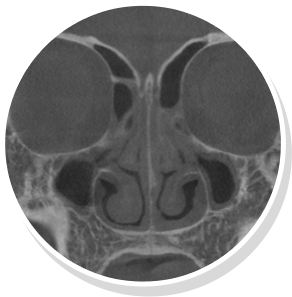

비염

비중격만곡증

축농증